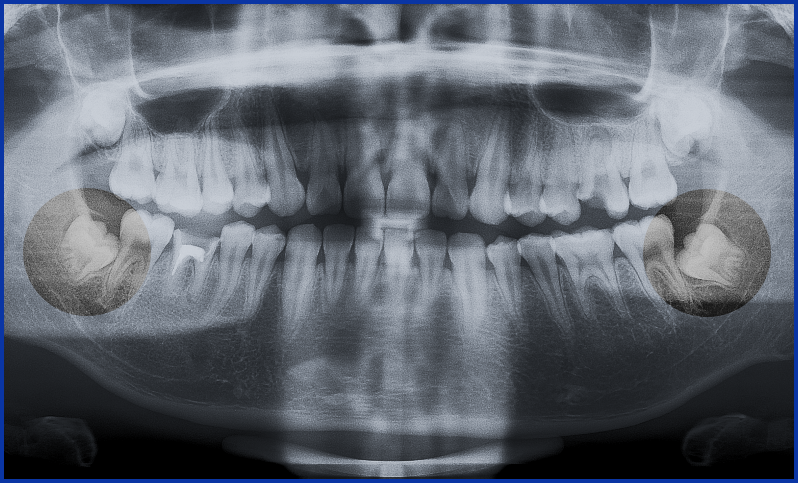

Có rất nhiều phân loại răng khôn khác nhau như phân loại của Winter, phân loại của Pell & Gregory. Tại Việt Nam trong các bảng giá nha khoa hẳn nhiên các bạn sẽ thấy có những hạng mục như nhổ răng khôn mọc kẹt, mọc lệch 45 độ, răng khôn nằm ngang, răng khôn mọc ngầm. Giới chuyên môn thường sẽ tìm những phân loại học thuật, để từ phân loại hình dung dễ dàng luôn quy trình điều trị. Tuy nhiên bệnh nhân thì chỉ cần biết những phân loại rất đơn giản , như phân loại trong bảng giá cũng được.

Răng khôn hay còn gọi là răng số 8 là răng hàm lớn số 3 là răng mọc cuối cùng, khi các răng khác đã mọc ổn định trên cung hàm. Răng khôn mọc trong khoảng từ 18 đến 25 tuổi. Hầu hết răng khôn mọc trong khoảng không gian nhỏ do bị giới hạn, nên thường bị mọc kẹt, mọc lệch, mọc ngầm.

Răng khôn là răng mọc sau cùng trong cung hàm khi các răng khác đã ổn định vị trí. Vì vậy khi mọc thường gặp tình trạng thiếu khoảng dẫn đến răng mọc lệch, mọc ngầm, lợi trùm, mọc kẹt gây biến chứng. Trong y khoa hiện đại nhiều trường hơợp răng khôn có nguy cơ gây biến chứng đều được nha sĩ chỉ định nhổ bỏ để tránh biến chứng.

Răng khôn hay còn gọi là răng số 8, răng mọc cuối cùng trên cung hàm. Răng khôn mọc ở độ tuổi từ 16 đến 26 tuổi khi mà các răng khác đã ổn định trên cung hàm nên răng khôn dễ thiếu khoảng và mọc lệch. Vậy nhổ răng khôn mọc lệch mọc lệch có ảnh hưởng gì không, có đau không, có nguy cơ gặp biến chứng gì và chi phí nhổ răng khôn mọc lệch là bao nhiêu chúng tôi sẽ giải đáp cho các bạn qua bài viết dưới đây.

Răng khôn là chiếc răng cối thứ 3 thường mọc độ tuổi từ 16 đến 26, răng khôn theo thuật ngữ y học gọi là răng số 8. Trên thực tế răng khôn mọc ngầm gây ra rất nhiều tác hại. Răng khôn không phải lúc nào cũng mọc đúng chỗ, đúng vị trí. Vì nó mọc sau cùng, mọc lên khi tất cả các răng khác đều mọc xong nên răng khôn hay bị mọc ngầm gây ảnh hưởng đến răng số 7, mọc ngầm gây viêm lợi.